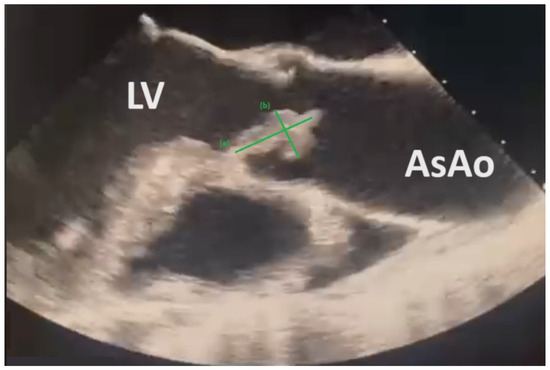

3. Case Report Description